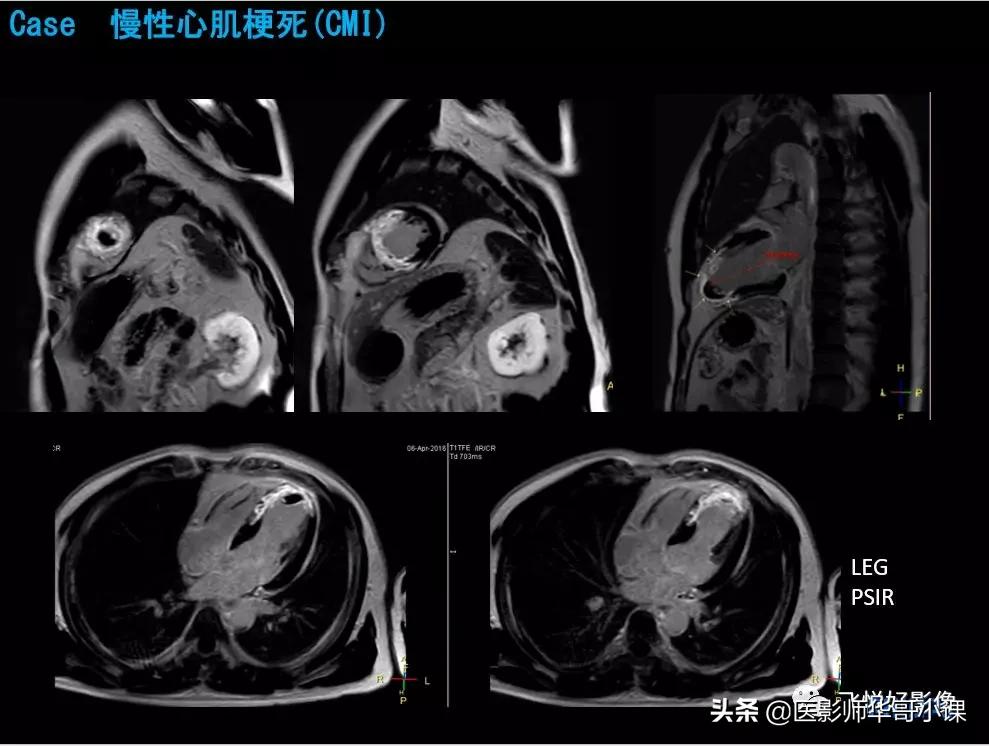

本期内容为无对比剂冠状动脉MRA、CMR心梗病例。飞利浦独特的极速冠状动脉MRA技术快至两分钟便可得到高质量的冠脉图像。